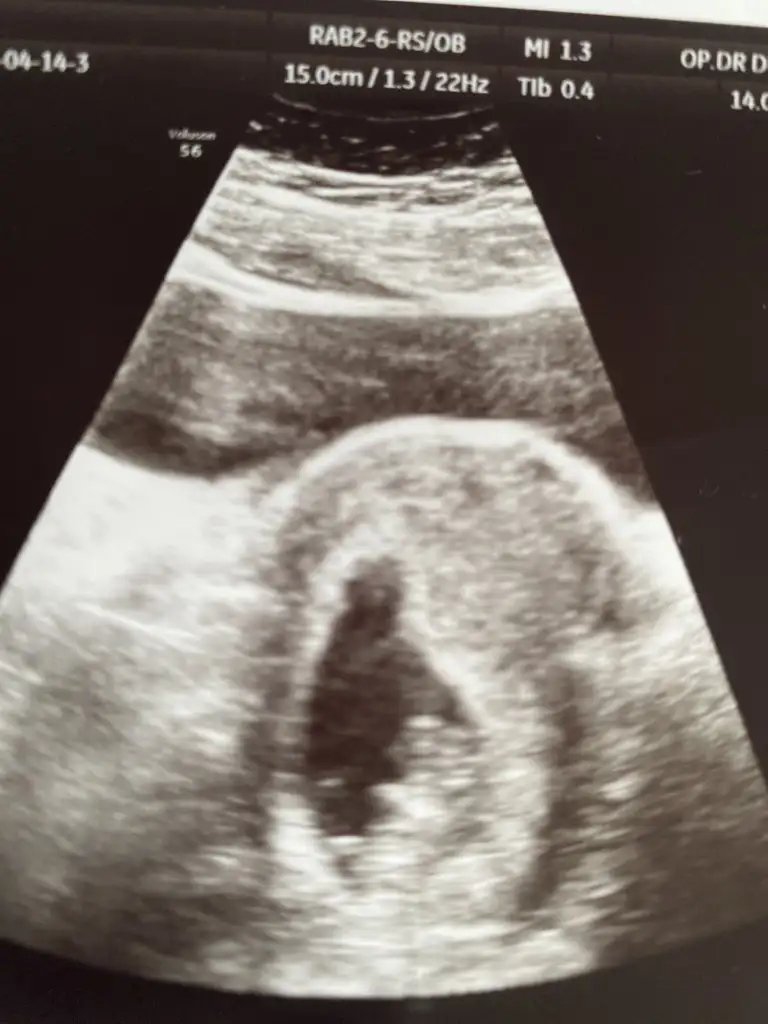

Erkek sanki yaa ayak sanki nubun üstüne çapraz atmışTahminde bulunurmusun

11 12 13 haftalar olmalıBenimkine de bakar mısınızEki Görüntüle 2828127

Benimkini de tahmin edebilirsinizErkek ve kız için 11 + 12+ yada 13 hafta usg görüntüsü olmalı açıklamalar asagıda yazıyorrabbim herkesin gönlüne göre nasip etsin inşallah .. ecmain